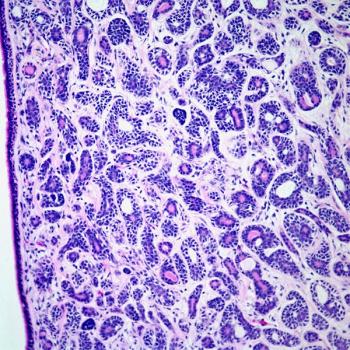

A 67-year-old man presents with a cough and history of weight loss of several weeks' duration. Chest imaging reveals the presence of a pulmonary mass. What is your diagnosis?